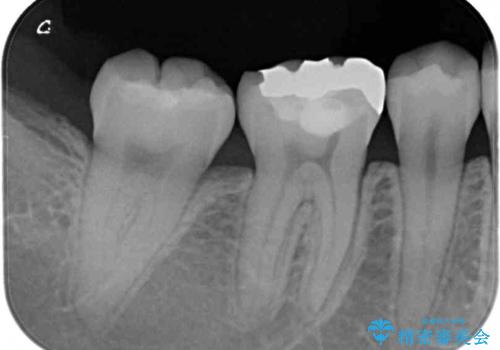

- 下の奥歯(右下7・左下7)にあって目立ってしまう銀歯を白くしたいとのことで来院された患者様です。

セラミックインレーにて修復治療を行うこととしました。